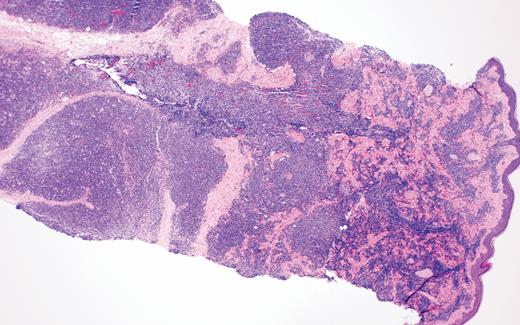

Biopsy of the affected tissue with histopathology and immunohistochemical stains is essential to making the correct diagnosis. The five most common phenotypic markers include CD4, CD56, CD123, CD303, and TCL1, though CD4-negative and CD56-negative cases have been reported.9,16 CD303, TCF4, and TCL1 are specific to pDCs and can help to solidify the diagnosis.15,16,18 BPDCN is negative for other lineage-specific markers such as MPO, T cells (CD3), B cells (CD20 and CD79a), and monocytes (CD11c, CD163, lysozyme).15,16,18 The plaque biopsied in Case 2 demonstrated a dense atypical infiltrate composed of medium-size cells with irregular nuclear contours, fine chromatin, and scant cytoplasm, resembling undifferentiated blast cells with frequent mitoses diffusely involving the dermis (Figure 5). The infiltrate was negative for B-cell and T-cell lineage markers and MPO while positive for CD4, CD123, and TCL1A, supporting a diagnosis of BPDCN.

Case 2 histopathology showing dense atypical infiltrate composed of medium-size cells with irregular nuclear contours, fine chromatin, and scant cytoplasm, resembling undifferentiated blast cells with frequent mitoses and scattered admixed foamy macrophages, some with hemosiderin diffusely involving the dermis. (A) Hematoxylin and eosin stain (2×); (B) hematoxylin and eosin stain (40×).